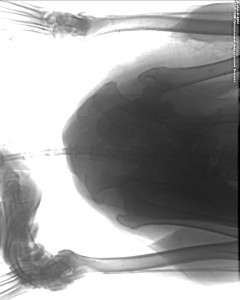

За счет средств Фонда были сделаны несколько снимков ,которые показали что ,тазовая кость имеет перелом в нескольких местах . С большим трудом удалось сделать ренгенологические снимки ,так как собака испытывала сильные боли , и не давала прикасаться к больному месту . Ветеринарным специалистом клинике собаке назначено лечение , будем надеяться, что все будет хорошо !